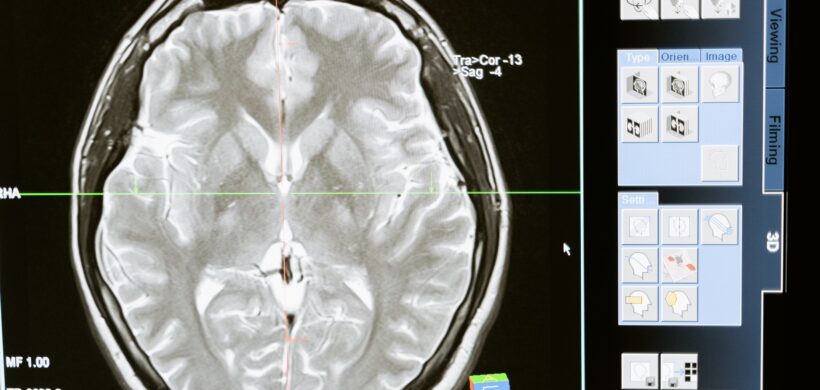

Atrofia cortical posterior: Enfoque neurooftalmológico

DRA. LUCIANA L. IACONO - NEUROOFTALMÓLOGA. HOSPITAL DE CLÍNICAS JOSÉ DE SAN MARTÍN, BUENOS AIRES, ARGENTINA. La atrofia cortical posterior (ACP) es una afección progresiva de índole neurológica que genera alteraciones visuales complejas con preservación del estado cognitivo hasta estadios avanzados de la enfermedad. Existe evidencia de compromiso degenerativo de los lóbulos occipitales, parietales y/o temporales posteriores. La ACP es catalogada como una de las variantes atípicas de la Enfermedad de Alzheimer siendo nombrada casi exclusivamente como su “variante visual”. La edad promedio de diagnóstico de esta afección es entre los 50 a los 60 años. En este artículo se hará referencia exclusivamente al compromiso visual de los pacientes con ACP, y a los hallazgos en la evaluación oftalmológica. Los pacientes con PCA suelen consultar, en primera instancia, por síntomas visuales, tales como: visión borrosa, falta de visión, o incapacidad para realizar actividades específicas como leer o conducir. Esta sintomatología, que se detallará a continuación, es difícil de discernir por el médico especialista y solo un examen visual minucioso y dirigido, y test específicos las pondrán de manifiesto: Simultagnosia: Consiste en la incapacidad de percibir o identificar diversos objetos en una misma escena y los pacientes tienen tendencia a cambiar la mirada de un objeto a otro sin poder verla su totalidad, lo que los lleva a alejarse de la misma para verla en su totalidad. Ataxia óptica: Es la falta de coordinación entre la visión y el movimiento de las manos, es decir, existe una incapacidad de llegar a los objetos guiados por las mismas, estando preservada esta habilidad al realizarla mediante otra modalidad sensorial como por ejemplo un sonido Apraxia ocular: Es un trastorno de la fijación, en el que el paciente no logra fijar un objeto específico en el campo visual, en ausencia de oftalmoplejía. Agnosia visual: Es la incapacidad para reconocer los objetos presentes, en ausencia de alteración visual primaria o afección de las funciones intelectuales del paciente. Alteración en la lectura: Está reportada como una de las afecciones más incapacitantes en la ACP. Se debe a la combinación de simultagnosia, apraxia ocular, y defectos campimétricos. Otras afecciones visuales: alteración del contraste, percepción de movimiento en estímulos estáticos, palinopsia, colores lavados, alteración de la sensibilidad de contraste y pérdida de la discriminación cromática. Defectos en el campo visual computarizado (CVC): La prevalencia de los defectos campimétricos varían notablemente en la literatura. Las hemianopsias homónimas o cuadrantanopsias son habitualmente reportadas en más del 50% de los pacientes con ACP y son reconocidos como un signo temprano. Posiblemente los cuadrantes inferiores pueden verse más comprometidos en esta afección, pudiendo deberse al compromiso de las radiaciones ópticas subyacentes. En conclusión, la ACP deberá tenerse en cuenta en pacientes jóvenes adultos que, por lo general ya han realizado múltiples consultas oftalmológicas previas, y que manifiestan alteraciones visuales poco claras pero severas, como la incapacidad para leer o conducir. También en aquellos pacientes donde se evidencia una hemianopsia o cuadrantanopsia homónima en la campimetría computarizada y no se logre identificar en las neuroimágenes lesiones, más allá de la ACP, que justifiquen dicha afección. Pulse para leer el artículo completo